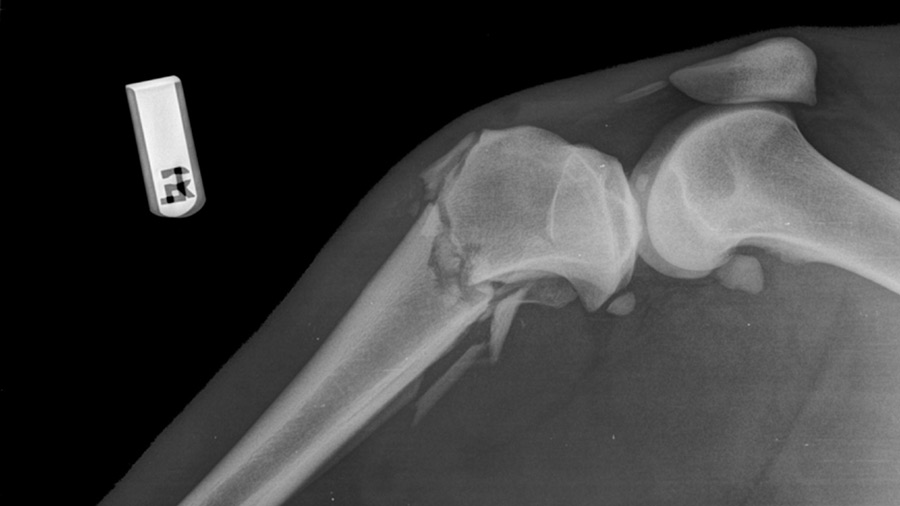

A 15-year-old lioness has recovered from open, comminuted fracture of the right proximal tibia and fibula and is back to inspiring zoo visitors, thanks to the efforts of a cross-specialty veterinary team led by an AO VET faculty member and guided by the AO principles.

“Her fractured limb was dangling useless, and she had an open skin wound. The long-term consequences of not fixing this fracture would have been chronic pain and permanent deformation of the limb. In the wild, she may not have survived,” Gasiorowski said.

After the patient was sedated with a dart gun, the surgical team—including Bergmann running anesthesia, technicians grabbing necessary supplies and taking intraoperative radiographs, and Gasiorowski and Monaco performing the surgery—had to move fast. The fracture was repaired with bone plates on both the medial (4.5 mm locking compression T-plate) and lateral (4.5 mm narrow locking compression plate) aspects of the tibia. Intraoperative radiographs were used to guide plate and screw placement.